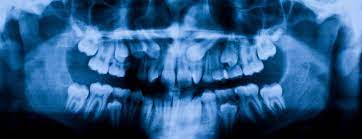

牙科射线照片可以提醒您的牙医您的硬组织和软组织的变化。对于儿童来说,X光片可以让牙医看到他们的牙齿和颌骨的发育情况。与医学射线照片一样,牙科射线照片可以让牙医评估您面部和口腔的任何损伤。

该数据集包含一个 zip 文件,其中包含三个文件夹。训练 - 测试 - 有效

因此您可以使用它们作为输入目录并使用 CNN、Yolo 或 SSD 创建一些图像分类。